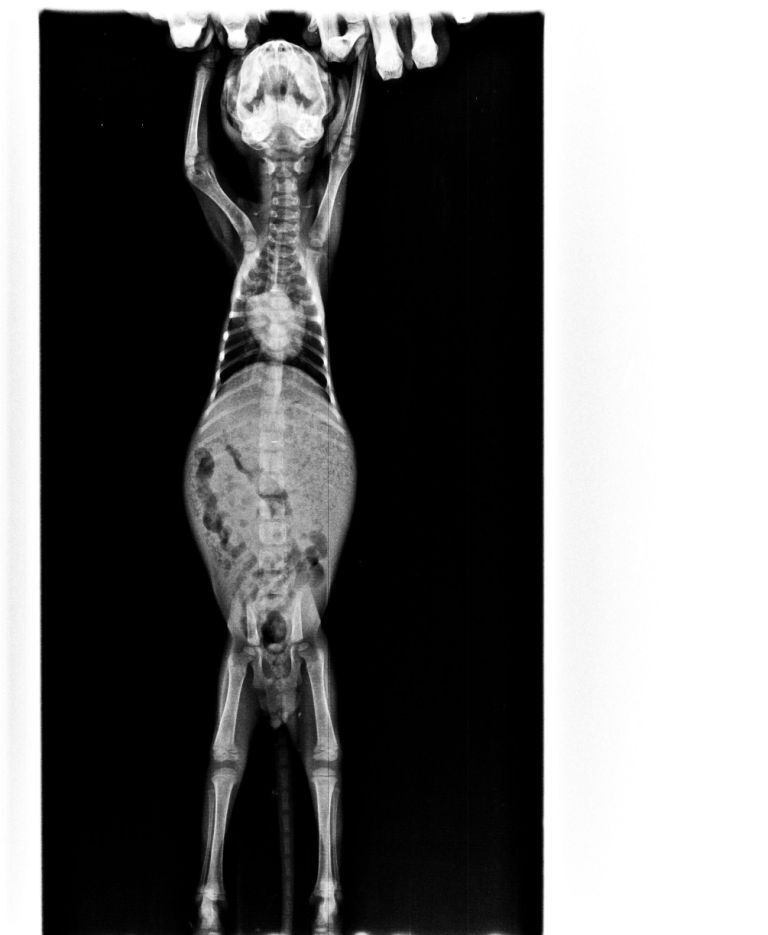

主題: 五股收容所領出雙眼全盲嚴重呼吸道感染小貓 申請者姓名: 臺北市支持流浪貓絕育計劃協會 花色: 申請日期: 2017-05-18 13:26:08 申請者部落格: 申請者臉書網址: 所在縣市/合作醫院: 台北市/極光動物醫院 治療費用: 18585元 需求人數: 39人 已結案 (2024-06-01 13:28:19) 報名人員: tnr x2(已付款)、章詠涵 x5(已付款)、jojolin(已付款)、Choco Chen x6(已付款)、陳奕隆(已付款)、Norman Wu(已付款)、Sean(已付款)、Peiyu、Peiyu x2(已付款)、Pe、Howl Liu(已付款)、Amirose Hsieh x2(已付款)、Erica Huang x2(已付款)、賴賴(已付款)、Bobo Li(已付款)、薇薇安(已付款)、pomelobubble(已付款)、林桂生 x2(已付款)、咪咪貓 x2(已付款)、Vita Hsiao(已付款)、Chacha&Vivi x2(已付款)、洪凱威 x2(已付款)、洪凱威 x2(已付款)、 候補人員: 動物病情說明: 2017年4月19日

志工從五股收容所中領出了一隻雙眼全盲的小貓

有嚴重呼吸道感染,在院中進行重症照護

不吃不喝需要灌食

除了每日進行的噴霧治療,還須搭配灌食以及保溫

由於小貓雙眼全盲,而嚴重的呼吸道感染使原先就未睜開的眼睛更密合

院方除了點藥水外,也需替小貓進行擦拭